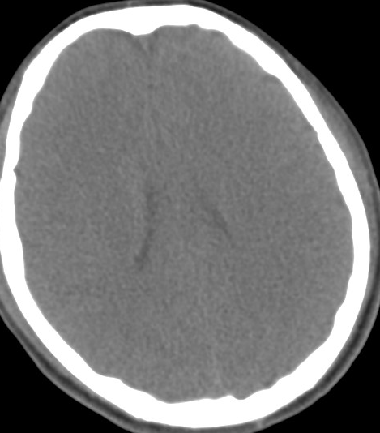

2014-10-5 CT